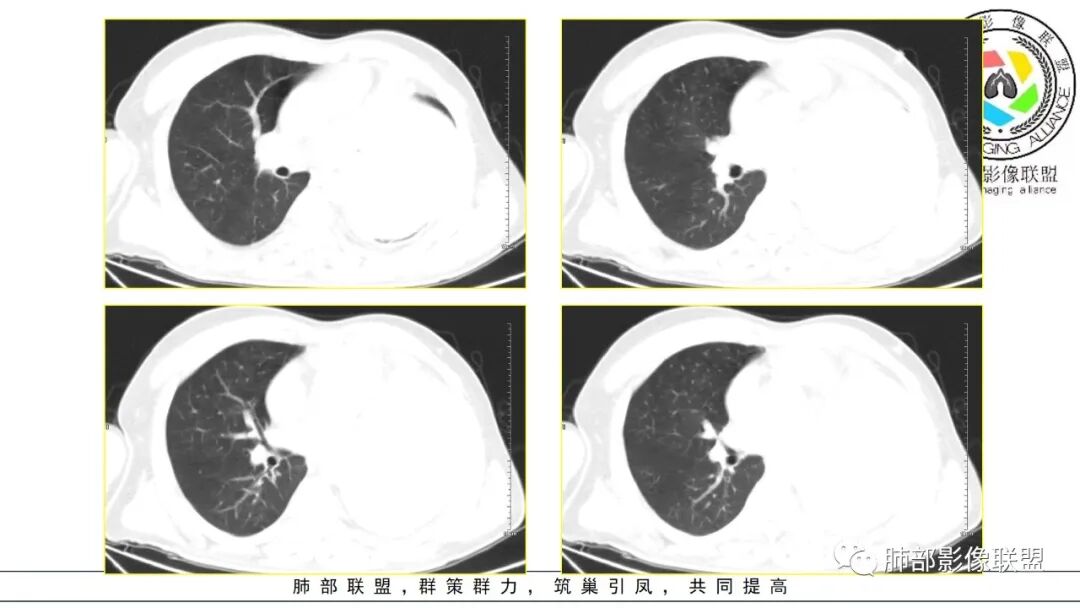

左肺巨大肿块,边缘光滑,密度不均,内可见多发低密度坏死,坏死边缘清晰,左肺支气管受压变窄闭塞,考虑左肺肉瘤样癌?鉴别滑膜肉瘤?

定位肺内,左下肺巨大肿块,边缘光整,密度不均,边缘少许钙化,中心坏死,外周强化,左肺支气管及心脏受压,考虑肉瘤样癌,鉴别滑膜肉瘤,SFT

左肺巨大肿块,边缘光滑清晰,内见多发低密度影,边界也比较清楚,左肺支气管受压变窄闭塞,恶性。

男,50岁,双下肢水肿10余天,发热3天。NSE、细胞角蛋白19片段增高。胸部CT:肺气肿背景,左下叶巨大肿块,边缘膨隆明显,与周围界限清楚,累及左肺门、左上叶,上叶支气管受压狭窄,下叶支气管截断,不均匀强化,湖泊样坏死,肿块边缘粗大点状钙化,肿块内血管影迂曲、模糊,蛇纹?考虑恶性,鳞癌?肉瘤样Ca?鉴别SFT。

2.左肺巨大块影,上部边界较清楚,占据胸腔大部,对于左肺,“占据”及“推移”兼而有之,左肺上叶支气管推移狭窄,下叶支气管截断。下肺动脉穿行!

3.病灶密度不均,轻度强化,坏死或液化范围甚大,边界可分辨,部分“壁”可见钙化。